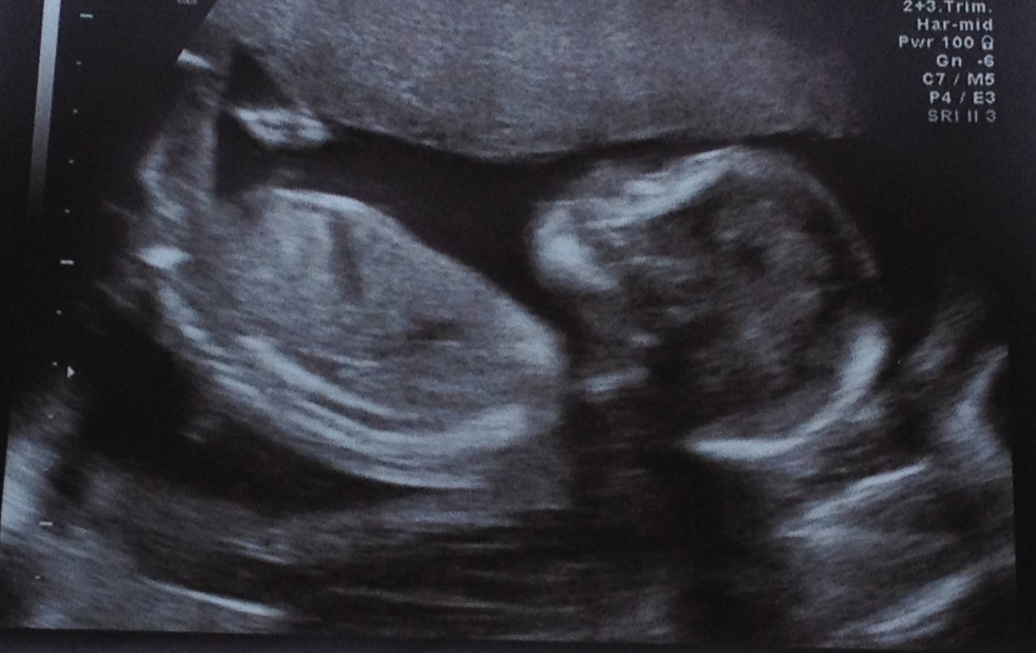

20 Week Scan Picture

We had our 20 week scan today and it was lovely to see bubs and everything is good which is great news :)

I personally can't see anything in the scan pics that might give me any clues but thought I would check with you guys too......

Anyone have any thoughts on the skull/gender etc??

No gender clues in the lower region...and that's a tricky skull. In one shot it looks boy, another girl. Looks like this bub wants to be team green too :))))))

great photos! I'm going to guess girl due to head shape its rounded more like a girl and looks like my daughters old scan photos!

I think the skull is very girly in the top photo Babymad!